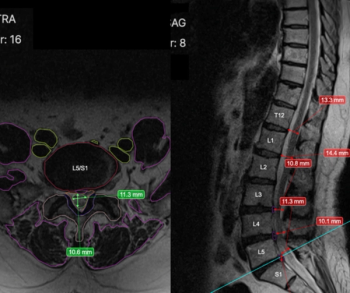

Trained on over five million spine MRI scans, the RAI software reportedly facilitates rapid pathology detection and enhanced consistency with disc measurement.